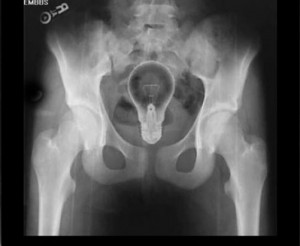

მობილური ტელეფონი

2 (1)